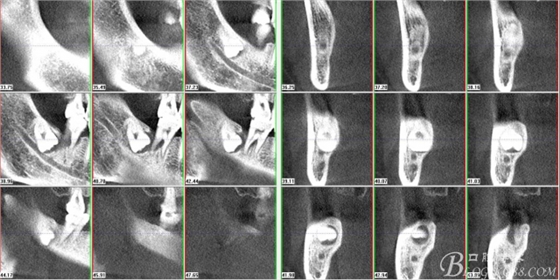

二、術(shù)前CBCT影像:

圖3.通過矢狀面和冠狀面來判斷48與下頜管及47的關(guān)系

圖4.水平方向48與47之間的關(guān)系

圖6.測量48頰、舌側(cè)骨板厚度。

圖7.測量牙冠近遠(yuǎn)中徑的大小及遠(yuǎn)中骨板的厚度